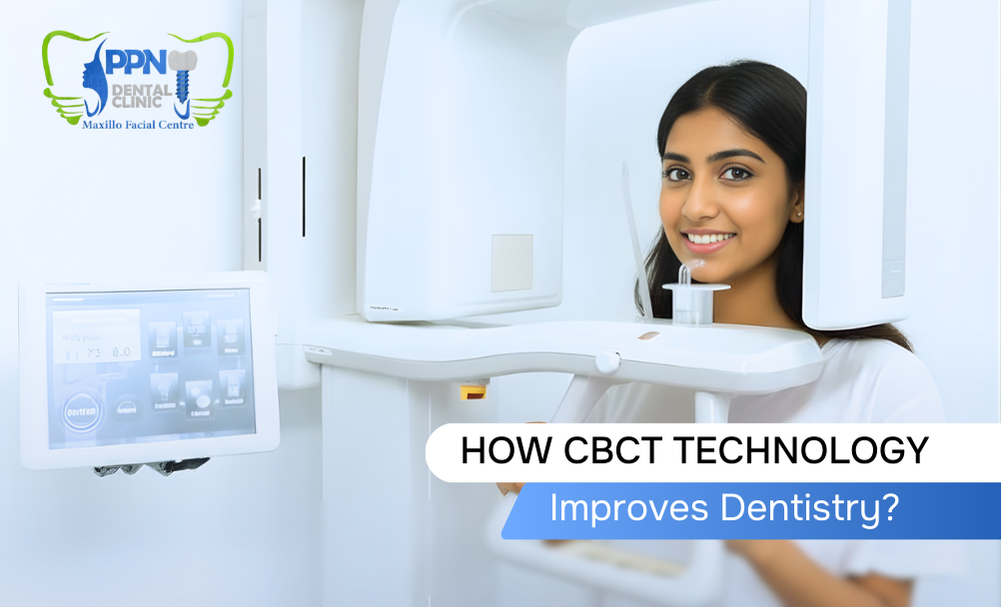

High-precision equipments for better outcomes

PPN Dental is equipped with modern technology that supports better patient care and smoother treatment processes.